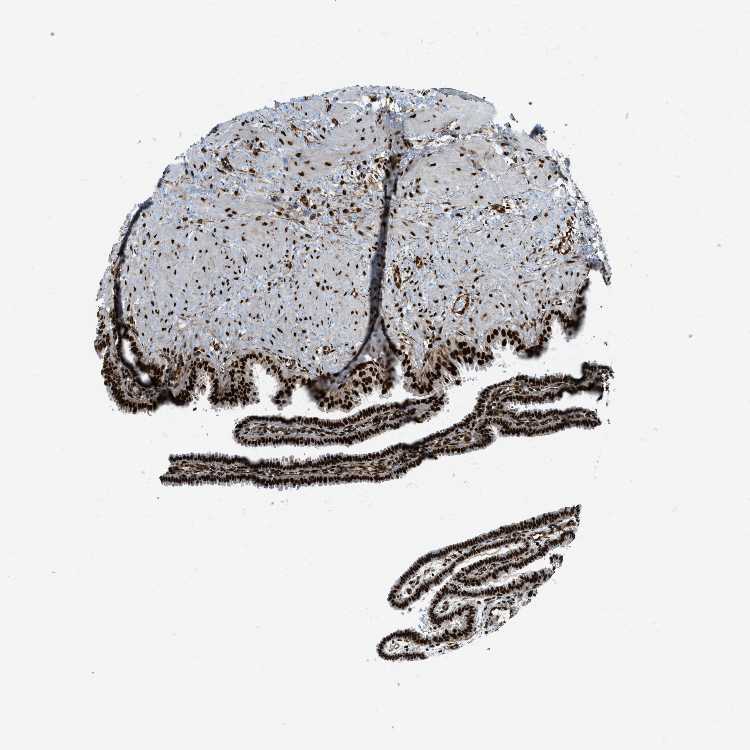

FALLOPIAN TUBE - Antibody stainingi

Antibody staining in the annotated cell types in the current human tissue is reported as not detected, low, medium, or high, based on conventional immunohistochemistry profiling in selected tissues. This score is based on the combination of the staining intensity and fraction of stained cells.

Each image is clickable and will lead to virtual microscopy that enables deeper exploration of all samples and also displays staining intensity scores, fraction scores and subcellular localization as well as patient and tissue information for each sample.

Antibody HPA016666

Glandular cells High